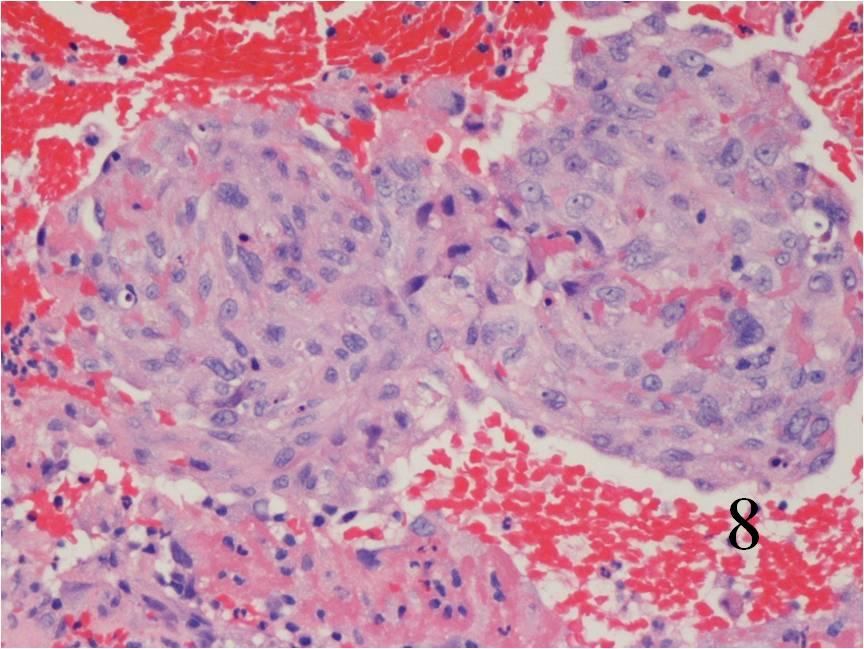

Fig. 7

Fig. 8

Fig. 7-8: Microscopic: Low (Fig. 7) and high (Fig. 8) power histology of an angiosarcoma shows abundant round to polygonal tumor cells. Fig. 8 shows nuclear atypia with mitotic activity. The cells are large with large irregular nuclei and significant pleomorphism. The cells appear somewhat epithelioid. The tumor stains positive for vimentin, Factor VIII and CD 34 (not shown in these photographs)